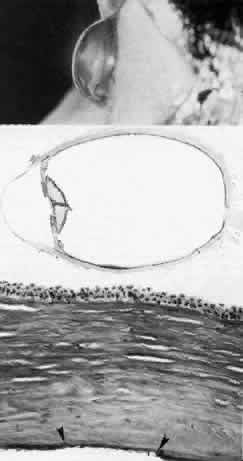

Fig. 4. Sclerocornea. Schematic drawing of ocular features Top left. In a minimally affected patient with additional findings of ptosis, strabismus, and hearing loss, only the peripheral cornea is opacified. Top center. In this advanced case with chromosomal translocation and multiple congenital abnormalities, the entire cornea is sclerified and the fine vascular arcades extend centrally from the conjunctiva and sclera. Top right. Light micrograph of anterior cornea shows edematous disorganization of epithelium, fragmentation of Bowman's membrane (B), and interstitial vascularization (V) (hematoxylin-eosin, × 200). Middle left. Transmission electron micrograph of normal human corneal stroma is shown for comparative purposes. Note uniform 240- to 260-nm collagen fibril diameter (× 50,000). Middle right. Transmission electron micrograph of sclerocornea at same magnification shows disorganized array of collagen fibrils that measure as much as three times normal diameter (× 50,000). Bottom. Transmission electron micrograph of posterior cornea shows abnormal Descemet's membrane of less than 1μm thickness (DM, bracketed) and attenuated endothelial cells (× 10,500). (Schematic. Grayson M: Diseases of the Cornea, p 32. St. Louis, CV Mosby, 1979; Top center and right. Rodrigues MM, Calhoun J, Weinreb S: Sclerocornea with an unbalanced translocation [17p, 10q]. Am J Ophthalmol 78:49, 1974)

Ultrastructural studies22,46,47 have shown the involved stroma to assume the morphologic features of scleral tissue, with irregularly arranged collagen fibrils of variable and immensely enlarged diameter for corneal tissue (up to 150 nm, comparable to normal scleral collagen). The precise lamellar organization of normal corneal stroma is not present; thus optical clarity is not achieved. Various abnormalities of endothelium and Descemet's membrane exist, from attenuation to focal absence. Descemet's membrane is generally thin, with multilaminar deposition of basement membrane-like collagen.

Pathophysiologically, sclerocornea may result from developmental arrest of limbal differentiation during neural crest migration, as occurs with the other mesenchymal dysgeneses.22